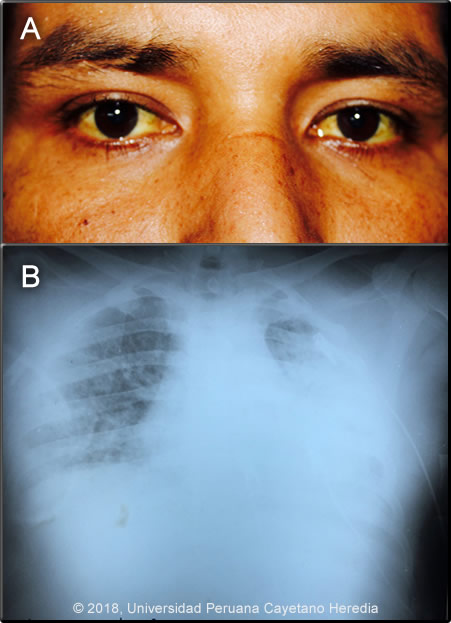

Past Medical History: Diagnosed in 2015 with HIV, (CD4=293 cells/mm3; viral load= 462,981 copies/ml. HAART (with zidovudine, lamivudine and efavirenz) was taken irregularly and stopped the medications two months ago with (CD4=18 cells/mm3; viral load=905,000 copies/ml. Epidemiology: Born in Pucallpa (jungle), moved to Ancash (highlands), at the age of 6 and has been living in Lima for the past 10 years. No known TB contact. Denies alcohol or drug consumption. Physical Examination: Pulse: 110; respirations: 28 SatO2:96% on 2l/min O2; BP: 102/61 mmHg; T:39,5C Patient in obvious respiratory distress. Skin: Pallor ++/+++, non-painful sacral ulcer 3x5cm with regular borders. (Image 1). Bilateral cervical lymphadenopathy. Chest: no rales in both lungs. Abdomen: normal bowel sounds, soft, non-tender, non-distended. No hepatosplenomegaly. Laboratory: Hemoglobin: 7.9 g/dl;, Hematocrit: 24%, WBC: 1,200; neutrophils:78%. Platelets: 95,000. Glucose: 106 mg/dl, Creatinine: 0.6 mg/dl. Alkaline Phosphatase: 1023 IU/l (N<126); LDH: 395 U/L (N=313-619); beta2 microglobulin: 3113 ng/ml (900-2700) Sputum AFB: negative x 3, culture pending. CT scan of the chest is shown (Image 2).

![]() Discussion: Histoplasma capsulatum was isolated from bone marrow culture. Image 3 shows diagnostic macroconidia with tuberculated typical thick walls that are large and round about 8-16 microns. Definitive diagnosis in these cases is made by fungal isolation (from bone marrow, blood or tissue samples including lymph nodes, skin or oral lesions) as a gold standard. Cultures are positive in about 75% of patients (AJTMH 2013;89:937). Urinary histoplasma antigen is very useful (97% sensitivity) but usually not available in developing countries. Direct observation of yeast cells from blood samples has low sensitivity (10%), better results are obtained from bone marrow samples. H. capsulatum is a dimorphic endemic fungus of worldwide distribution but is most common in North America and Latin America. In highly endemic areas more than 80% of persons are infected by age 20, often sub-clinically. Bats, which often live in caves, are frequently infected. Acquisition is inhalational with principal sites of disease in lungs, lymph nodes, liver, spleen, bone marrow, adrenals and the GI tract. In normal hosts, a self-limited pulmonary infection with mediastinal adenopathy is most common, but opportunistic disseminated infections in patients with depressed immunity, especially those with AIDS, is frequent. Endemic areas are the Mississippi, Ohio and St. Lawrence valleys in the USA, the Caribbean, Mexico and Latin America, South East Asia and Africa. Histoplasmosis is endemic in Latin America including Peru, the fungus is predominantly found in jungle areas. The reported incidence among advanced HIV-infected patients varies from 8% in Panama to 42% in French Guyana, being the first or second opportunist infection in these patients (AIDS 2016;30:167). A necropsy study of 16 patients who died with advanced AIDS in Lima, Peru found that 3 (19%) had disseminated histoplasmosis (Pathol Res Pract 2006;202:767). Exogenous acquisition or reactivation of a latent foci, as in this case are the modes of acquisition. Histoplasmosis is the most common endemic mycosis among HIV-infected patients. Progressive disseminated histoplasmosis (PDH) as demonstrated by this patient is the most common manifestation of histoplasmosis in AIDS patients. The Chest CT scan (Image 2) showed an interstitial infiltrate mainly composed of micronodules compatible with a milliary pattern. The differential diagnosis of these CT findings in a patient with HIV includes TB, PCP, penicilliosis (found mainly in Southeast Asia) and lymphoma. The differential diagnosis of the skin lesions in this patient includes herpes simplex infection, tuberculosis, paracoccidioidomycosis and cancer. PDH may be the first manifestation of advanced AIDS in endemic areas, a study among 89 patients with advanced AIDS in Colombia found 45 (51%) with PDH (AJTMH 2016;95:918); interestingly, 35% had TB as well. Predictors of PDH were significant weight loss, hepato or splenomegaly, skin lesions and hematologic abnormalities (mainly pancytopenia), all of them seen in this patient. Pulmonary involvement is seen in about 50-70% with non-specific manifestations (dry cough, chest pain, dyspnea); 50-70% of patients have abnormal radiologic findings; diffuse interstitial infiltrates or reticulonodular infiltrates are the most common abnormal findings. PDH is associated with high mortality rates, a study among 101 confirmed cases in Guatemala found a crude mortality rate of 44% with a median survival time of 19 days (AJTMH 2017,97:42); a Peruvian case series from a single center found that 59% (16) of 27 HIV-infected patients with histoplasmosis had PDH, with a mortality rate of 22% (Rev Chilena Infectol 2017;34:365-9). Co-infections are common. Among 45 patients in Colombia, 23 had other infections, 70% had TB and 13% had PCP or cryptococcosis (Med Mycol Case Rep 2018;19:45) USA treatment guidelines (Clin Infect Dis 2007;45:807) recommend induction therapy with liposomal amphotericin B (or amphotericin B deoxycholate in persons with low risk for nephrotoxicity) for 1-2 weeks followed by itraconazole for at least 1 year, with dosing guided by measurement of serum drug levels. Suppressive therapy with itraconazole is stopped if patients have received one year of itraconazole therapy, have negative blood cultures, low levels of urinary antigen (<2ng/ml), a CD4 cell count >150 cells/mm3, and patients are on HAART. Initiation of HAART should not be delayed; IRIS is rare and usually not severe. Our patient was started empirically on anti TB treatment with standard 4-drug therapy and is currently receiving amphotericin deoxycholate. He will be started on ART within 2 weeks of induction therapy with amphotericin B. |